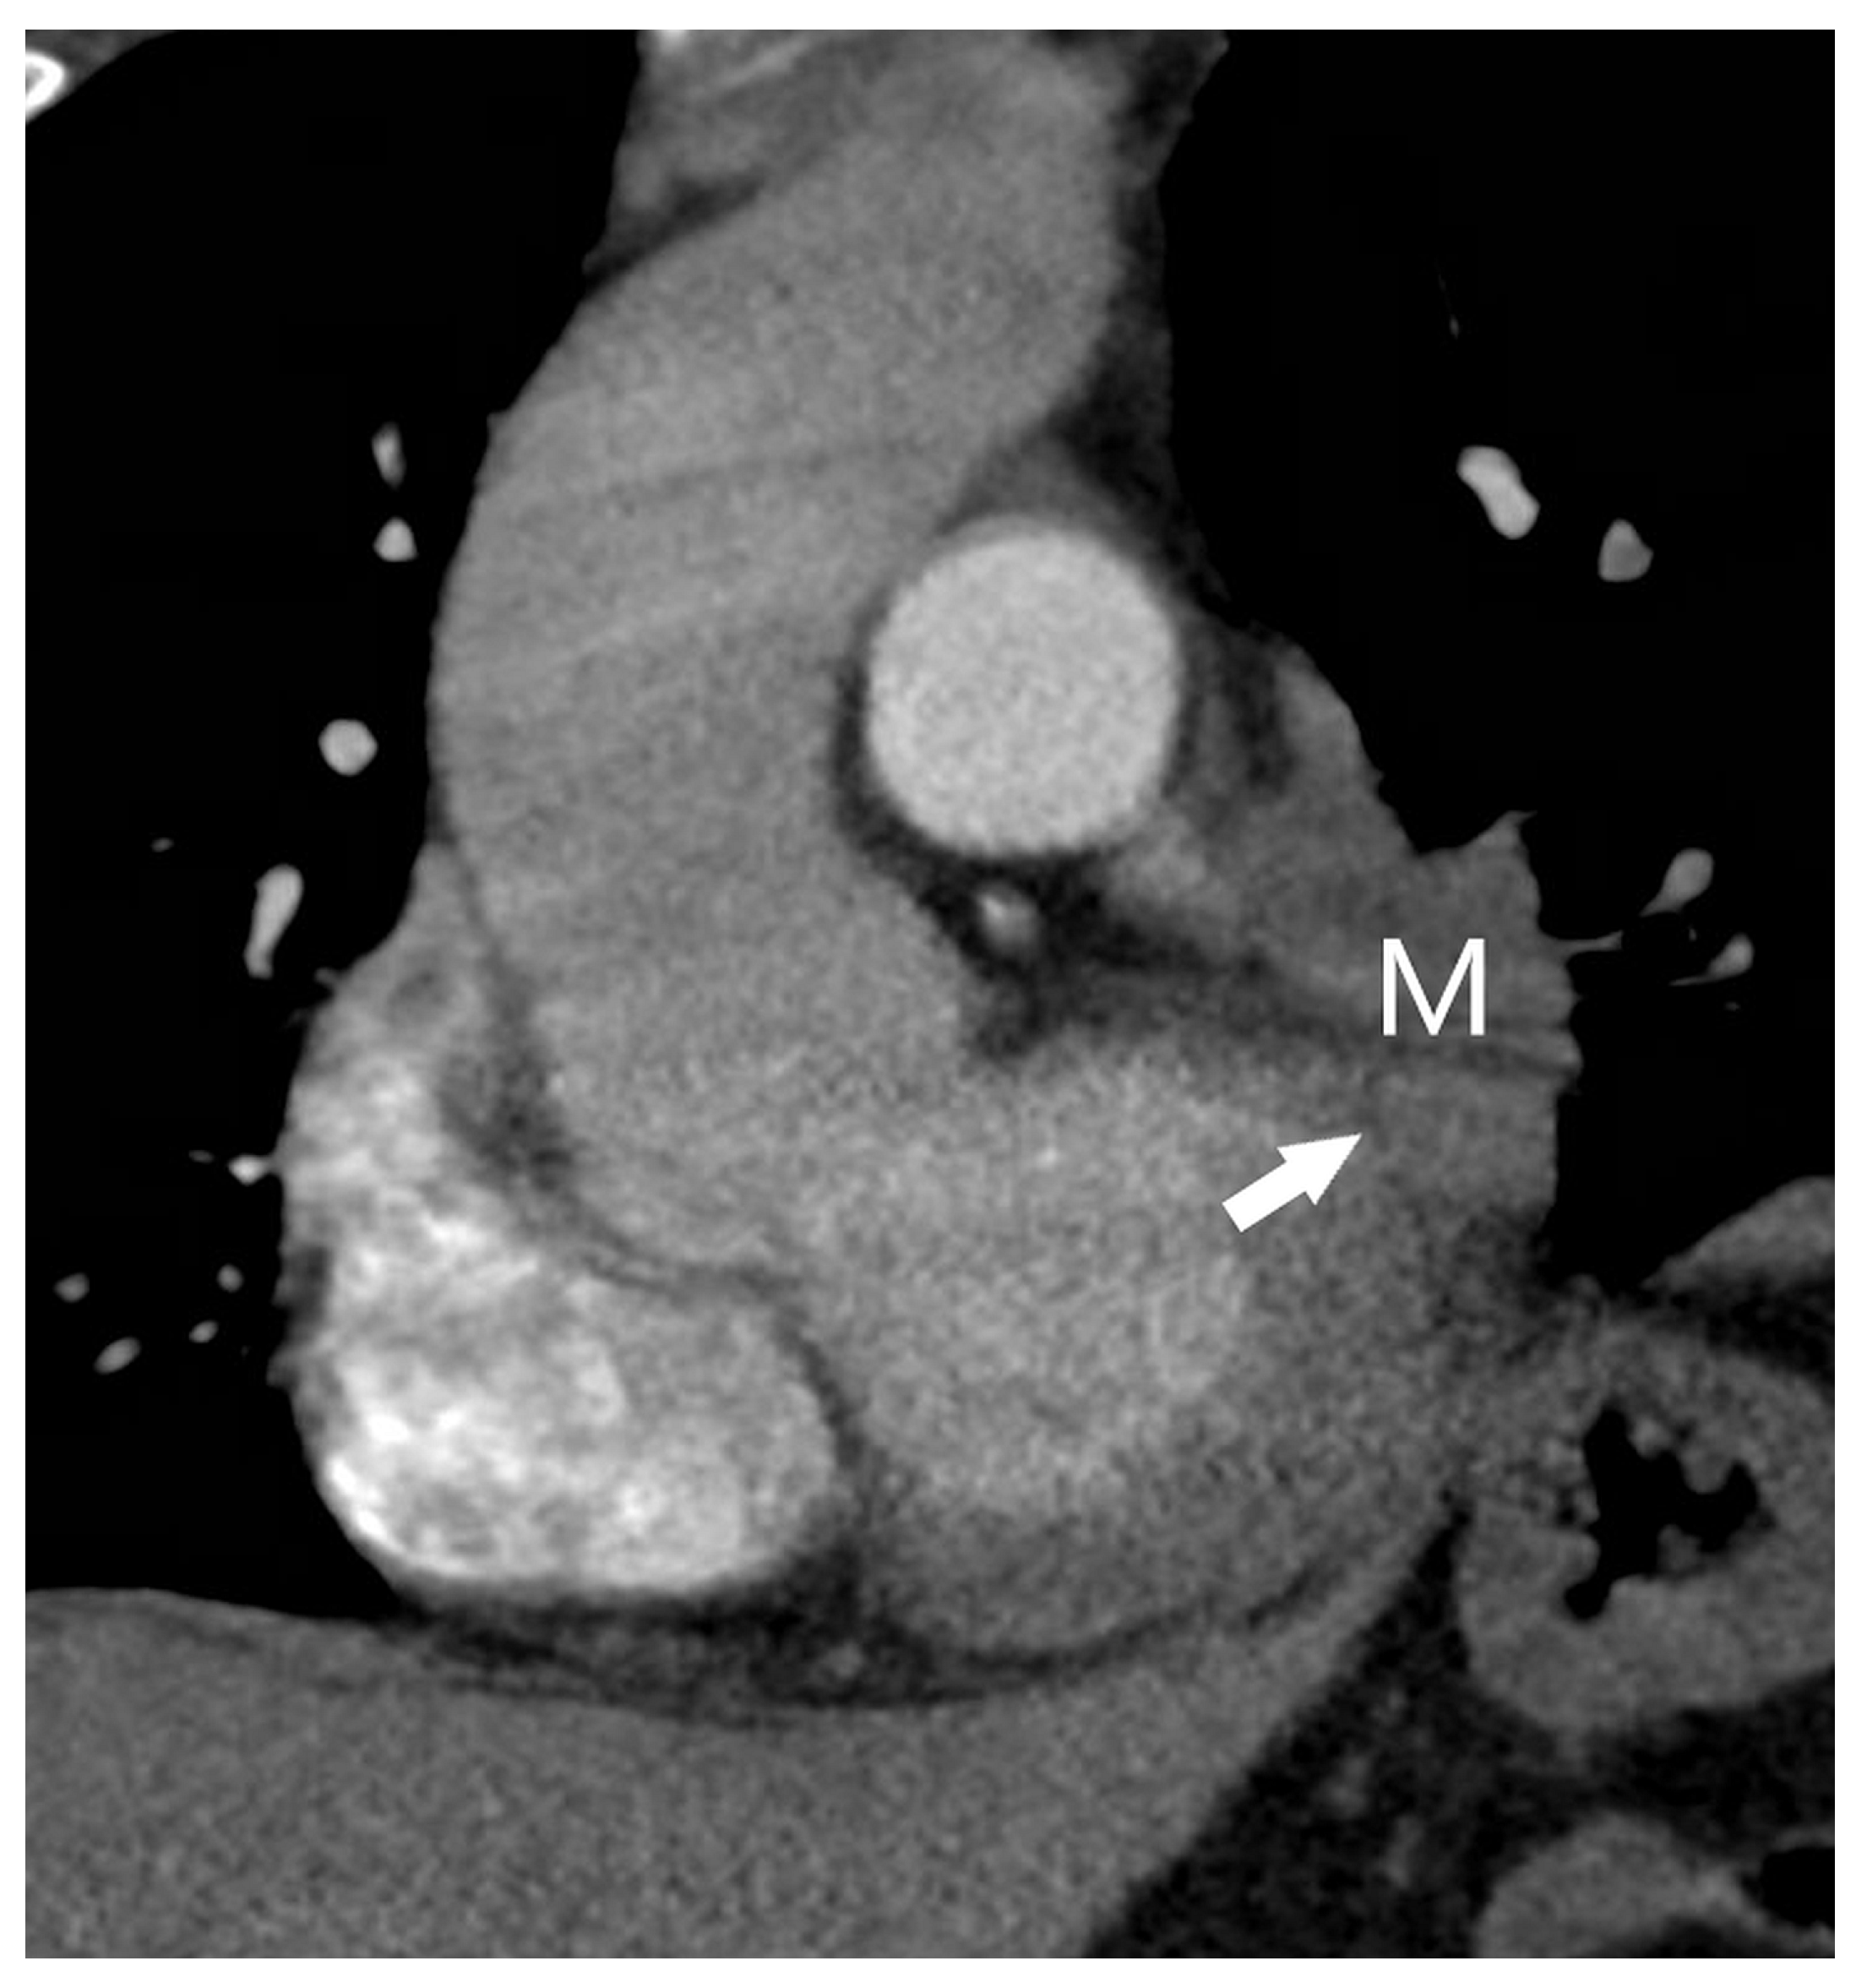

| T4 | Tumor > 7 cm in the greatest dimension Invasion of the mediastinum, thymus, trachea, carina, recurrent laryngeal nerve, vagus nerve, esophagus, or diaphragm Invasion of the heart, great vessels (aorta, superior or inferior vena cava, intrapericardial pulmonary arteries or veins), supra-aortic arteries, or brachiocephalic veins Invasion of subclavian vessels, vertebral body, lamina, spinal canal, cervical nerve roots, or brachial plexus Separate tumor nodule(s) in a different ipsilateral lobe than that of the primary | Signs of mediastinal invasion: infiltration of the mediastinal fat or structures that indicate the T4 stage, tumor–mediastinum contact length of more than 3 cm, an obtuse angle between the tumor and the mediastinum [37] Signs of vascular invasion: disappearance of the fat layer between the mass and the vessel, the angle between the mass and vessel wall >90°, a stenosis or deformation of the vascular lumen [41,42] |